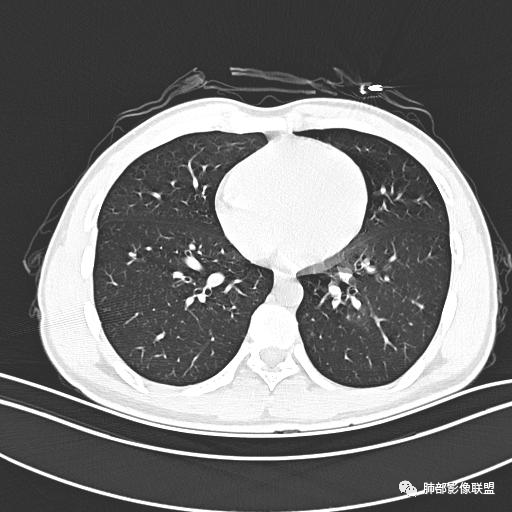

【每日晨读】年轻男性,发热+皮疹+肺内点晕

主  诉:发热、全身皮疹2天。

现病史:患者源于2天前受凉后出现发热,最高体温为38.5℃,且颜面部出现少量皮疹,无鼻塞、流涕、咳嗽、咳痰,未在意而未作特殊处理,次日全身皮疹逐渐增多至全身,伴轻度瘙痒,在当地卫生所给予抗病毒、抗感染治疗(具体用药不详)体温有所下降,但皮疹无明显消退,无腹痛、头痛,食欲无明显减退,为进一步诊治,遂于今日急来我院求治,患者目前精神尚可,体力正常,食欲正常,睡眠正常,体重无明显变化,大便正常,排尿正常。

小强:青年,发热,皮疹;双肺散在结节,周围磨玻璃,点晕征,疱疹病毒感染,鉴别荚膜组织胞浆菌,结核。 大雄:青年,急性起病,发热伴全身皮疹2天,抗病毒治疗体温有下降。双肺随机分布大小不等类圆结节,“点晕征”。考虑水痘-疱疹病毒(VZV)血播询问接触史,查体皮疹分布以及形态基本可诊断。 王开金江津中心医院呼吸科:青年男性,起病急,病程短,以发热,皮疹为首发症状,感染指标以单核细胞升高为主,胸部ct双肺多发结界,周围有晕,点晕表现,随机分布,同意於老师意见,水痘疱疹病毒血流感染累及肺。 王秀仙:双肺多发大小不等结节,周围有晕,边缘模糊,呈点晕征表现。青年,急性起病,发热伴全身皮疹2天,抗病毒治疗体温有下降。考虑疱疹病毒。鉴别荚膜组织胞浆菌。 傅昌瑜:19岁男性,发热、全身皮疹2天,单核细胞增高,双肺多发结节,结节边缘见边界不清磨玻璃影。点晕征+发热、全身皮疹+单核细胞增高——考虑水痘-带状疱疹病毒肺炎。 一切∮随缘:年轻男性,发热,皮疹两天,实验室,CRP,PCT增高,影像:双肺多发散在磨玻璃结节,边界欠清,大小不等,呈点晕征改变,以血管束周围分布为主,局部血管束略增粗,其它无明显改变,考虑:1:病毒性肺炎(水痘疱疹病毒?不知道皮肤有无改变)2:真菌(组织胞浆菌,血管侵袭性肺曲霉)3:GPA4:寄生虫(实验室没有看到嗜酸细胞增高) 赵山河:双肺散在结节,周围有晕,边缘模糊,呈点晕征表现。青年,急性起病,发热伴全身皮疹2天,抗病毒治疗体温有下降。考虑水痘—疱疹病毒感染。洪桥爱:青年男性,发热、皮疹2天,伴瘙痒,皮疹于面部首发,之后进展至全身,虽然没有对皮疹进行描述,但是从出疹时间及皮疹进展情况,伴瘙痒,应该就是个水痘患者;CT提示双肺随机分布结节影,部分结节伴有边界不清晕征,考虑水痘血播肺。 刘强:年轻男性,急性起病,皮疹,发热,抗感染治疗体温下降,说明有效。影像表现为散在点晕征,感染类疾病谱(疱疹病毒,真菌,结核),结合年龄,皮肤皮疹,考虑水痘-疱疹病毒性肺炎。 小兜:男性,19岁,发热皮疹两天,颜面部至全身,CRP,降钙素及单核增高。CT示双肺散在小结节,周围伴磨玻璃影,点晕征,考虑为水痘-带状疱疹病毒(varicella-zoster virus,VZV)肺炎 必有路:青年,皮疹+发热+“点晕征”→水痘-疱疹病毒(VZV) 许慧良:青年男性患者,发热、皮疹2天,体温最高38.5℃,第3天皮疹扩展至全身,伴瘙痒,胸部CT:双肺多发随机分布的小结节,结节周边见边界模糊的晕征,考虑水痘病毒感染流心明智:男,19,急性起病,发热伴全身皮疹2天。出疹顺序头→全身,抗病毒有效。胸部CT:两肺多发大小不等类圆形实性小结节影,随机分布,结节周围环绕GGO,边界模糊,呈点晕征。出疹特点是关键,未提示。考虑:血播病毒性肺炎,水痘-疱疹病毒?麻疹?鉴别荚膜组织胞浆菌、TB、血管炎、寄生虫等。 浪迹天涯:病灶多为5-10mm大小结节,结节周围可见磨玻璃样的晕环,常多发,可分布于肺内任何区域,考虑水痘—带状疱疹病肺炎如果短时间内有新的一个区域浸润,更加能说明,